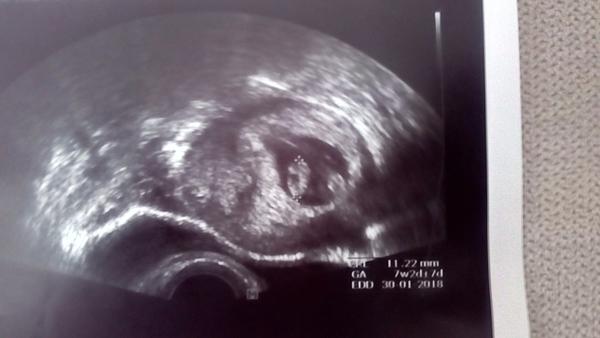

Ahoj holky,dnesni kontrola dopadla dobre.Merime 3cm,podle ultrazvuku dneska jsme 10+0tt a termin porodu se nam posunul z 30.1.2018 na 25.1.2018.Tyden nam odpovida podle MS.Dostala jsem tehu prukazku kde mi doktorka napsala termin porodu 2017 ale ja si toho vsimla az doma tak jsem si to prepsala ze 7 na 8.Dneska jsem dostala plno brozurek a plno terminu a do toho jsem se jeste dozvedela od mamky,ze vcera mela babicka pohreb,ze mi to nechtela vcera volat ze vi ze jsem tehotna.Ze zemrela minuly tyden ve spanku.Takze dobre i spatne zpravy.V pondeli 10.7.na lacno na krev,donest moc.Ve stredu 19.7.jdeme na 1 screening a pak v pondeli 31.7.na kontrolu.Doktorka mi rekla ze si mam zajit k obvodni doktorce a zubarce,nevim teda kdy,to mi nerekla kdy se tam tak chodi nebo do kdy.